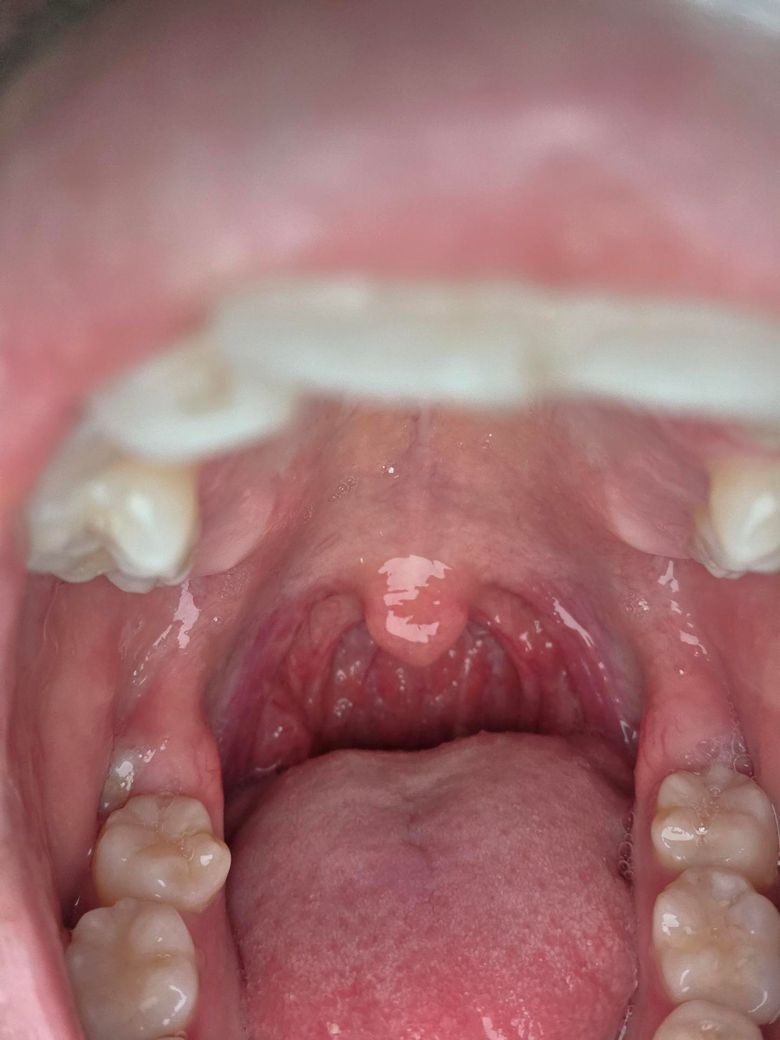

오늘 아침부터 동생이 감기에 걸렸는데 저는 지금 수험생이라 웬만하면 감기안걸리는게 나은데 심한편인가요? 목이 좀 아픈데 답변부탁드러요

• 1번 째 사진

직접 봐야 정확하게 판단이 되겠으나 사진상으로는 인두쪽에 발적이 동반되어있어 인두염으로 보입니다. 물 많이 마시고 충분히 휴식을 취하시는게 좋겠고 많이 아프시면 부루펜류의 소염제를 드시는게 도움이 됩니다. 열이 나거나, 많이 힘들면 진료를 보시는게 좋겠습니다. 참고하시기 바랍니다.